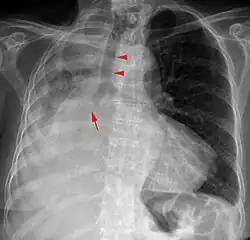

Ein Mediastinalshift oder eine Mediastinalverlagerung bezeichnet die Verschiebung des Mediastinums aus der Mittellinie des Thorax nach links oder rechts. Der Begriff wird in der Röntgendiagnostik verwendet.

Ursächlich ist entweder eine Verminderung des Volumens der Thoraxhälfte auf der Seite, zu der das Mediastinum verlagert ist, oder eine Vermehrung des Volumens auf der anderen Seite.

Ursachen für eine Volumenminderungen in einer Thoraxhälfte sind zum Beispiel

- Atelektase eines Teils oder der ganzen Lunge auf der Seite z. B. durch einen Tumor

- Zustand nach Resektion eines Teils oder der ganzen Lunge auf Seite

- Narbige Schrumpfung zum Beispiel nach Tuberkulose oder Trauma

- Fehlanlagen der Lunge